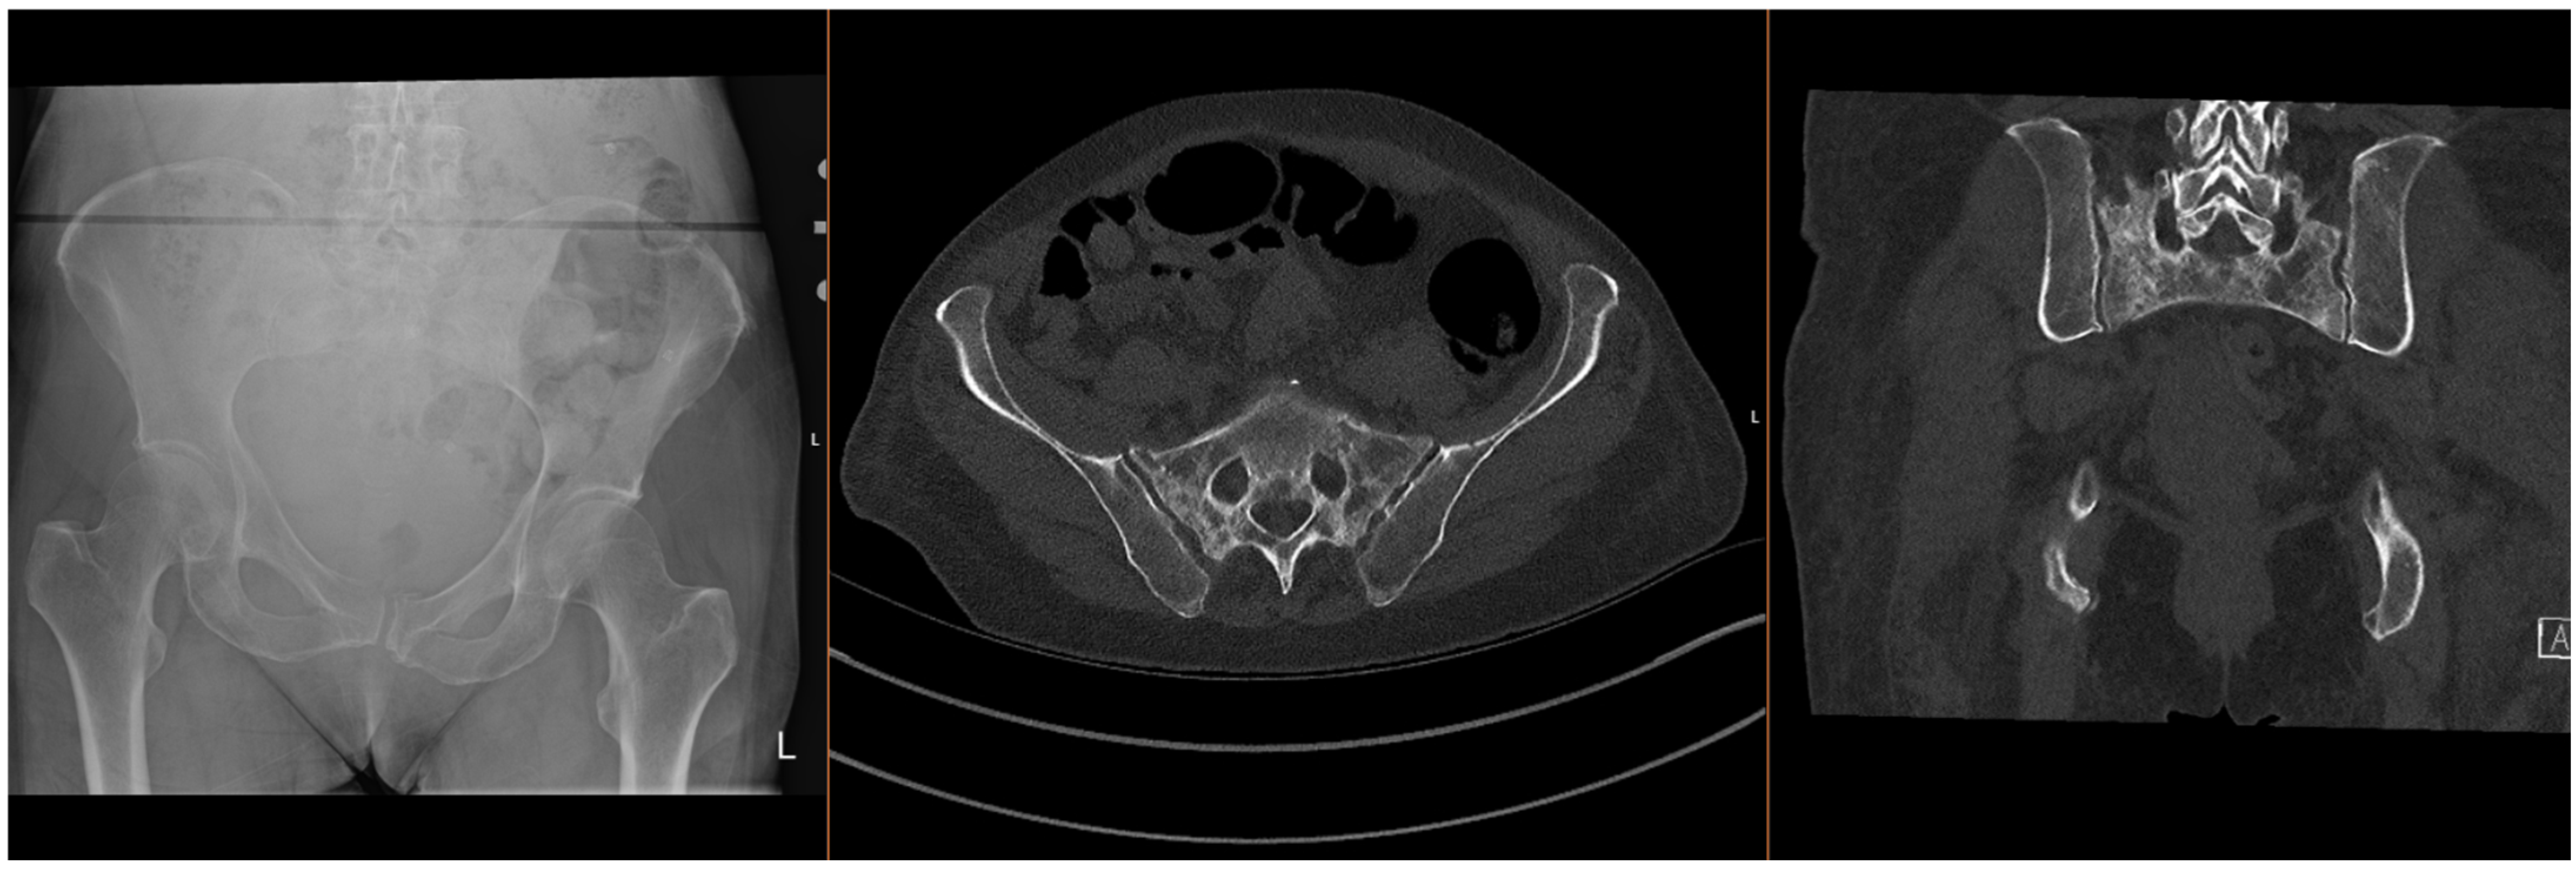

Figure 2.

Radiographs and CT images demonstrating common FFP: comminuted bilateral sacral fractures.